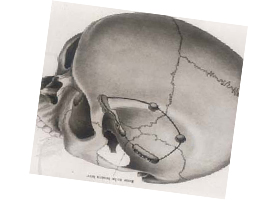

| 外傷 | |||

| (1)急性硬膜外血腫 | 2 | 0 | 0 |

| (2)急性硬膜下血腫 | 5 | 0 | 1 |

| (3)減圧開頭術 | 0 | 0 | 1 |

| (4)慢性硬膜下血腫 | 39 | 16 | 11 |

| その他 | 3 | 0 | 0 |